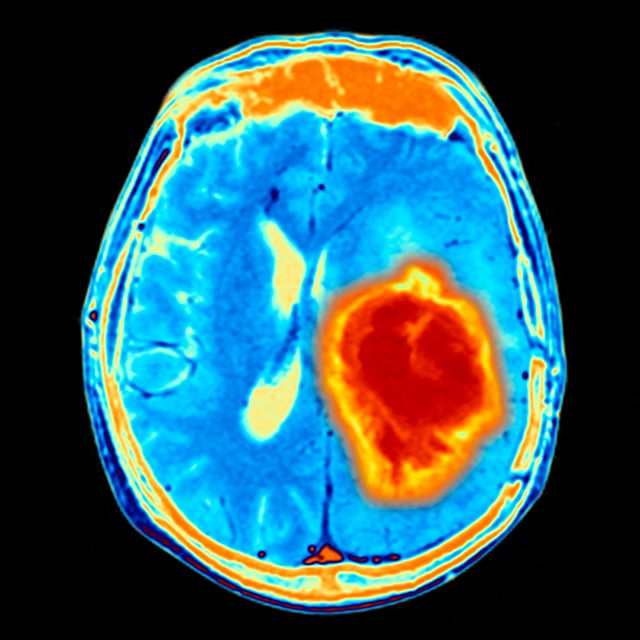

Astrocytoma is one of the most common types of brain tumors that can develop in children. It arises from a specific type of cell in the brain, called an astrocyte. Astrocytomas are divided into subgroups based on their grade and their location in the brain.

The symptoms of low-grade cerebellar astrocytoma usually lead to an imaging study of the brain. Sometimes the initial study is a CT scan, but an MRI scan is usually required to determine the exact location of the tumor and its relationship to other brain structures. Most cerebellar astrocytomas occur on one side in the cerebellar hemisphere. Fluid-filled cysts are common features of these tumors.